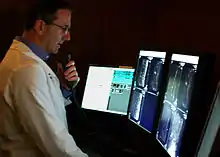

The modern practice of radiology involves several different healthcare professions working as a team. The radiologist is a medical doctor who has completed the appropriate post-graduate training and interprets medical images, communicates these findings to other physicians by means of a report or verbally, and uses imaging to perform minimally invasive medical procedures.[1][2] The nurse is involved in the care of patients before and after imaging or procedures, including administration of medications, monitoring of vital signs and monitoring of sedated patients.[3] The radiographer, also known as a "radiologic technologist" in some countries such as the United States and Canada, is a specially trained healthcare professional that uses sophisticated technology and positioning techniques to produce medical images for the radiologist to interpret. Depending on the individual's training and country of practice, the radiographer may specialize in one of the above-mentioned imaging modalities or have expanded roles in image reporting.[4]

Teleradiology is the transmission of radiographic images from one location to another for interpretation by an appropriately trained professional, usually a radiologist or reporting radiographer. It is most often used to allow rapid interpretation of emergency room, ICU and other emergent examinations after hours of usual operation, at night and on weekends. In these cases, the images can be sent across time zones (e.g. to Spain, Australia, India) with the receiving Clinician working his normal daylight hours. However, at present, large private teleradiology companies in the U.S. currently provide most after-hours coverage employing night-working radiologists in the U.S. Teleradiology can also be used to obtain consultation with an expert or subspecialist about a complicated or puzzling case. In the U.S., many hospitals outsource their radiology departments to radiologists in India due to the lowered cost and availability of high speed internet access.

Teleradiology requires a sending station, a high-speed internet connection, and a high-quality receiving station. At the transmission station, plain radiographs are passed through a digitizing machine before transmission, while CT, MRI, ultrasound and nuclear medicine scans can be sent directly, as they are already digital data. The computer at the receiving end will need to have a high-quality display screen that has been tested and cleared for clinical purposes. Reports are then transmitted to the requesting clinician.